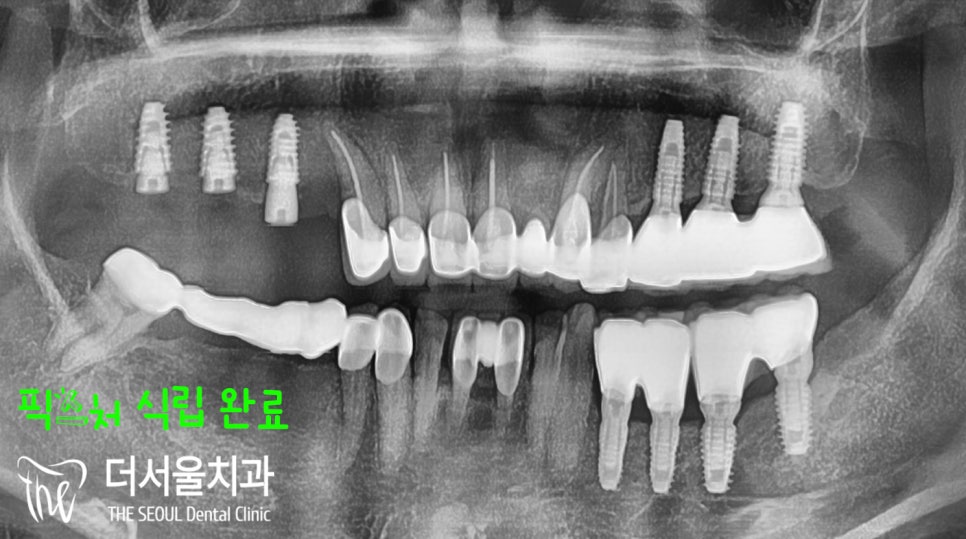

『컴퓨터 분석 시뮬레이션』

각각 심어야 될 위치를

컴퓨터 분석 프로그램을 이용하여

문제가 되는 것을 파악하고

어떤 조치를 취할지 계획을 수립합니다.

조심해야 될 것들은 꼼꼼히 체크하여

수술 후 부작용을 겪지 않게끔 합니다.

골밀도가 낮았던 것이 있었으나,

식립하는데 있어 큰 문제는 없었습니다.

수립된 계획을 바탕으로

장지동치과 의료진은

재료 선택 및 수술을 진행합니다.

우선은 어금니 위치에

픽스처를 심어드렸습니다.

별다른 문제없이 깔끔하게 잘 심어졌으며,

뼈와 튼튼히 붙어있을 수 있도록

골유착이 되는 기간을 가졌습니다.